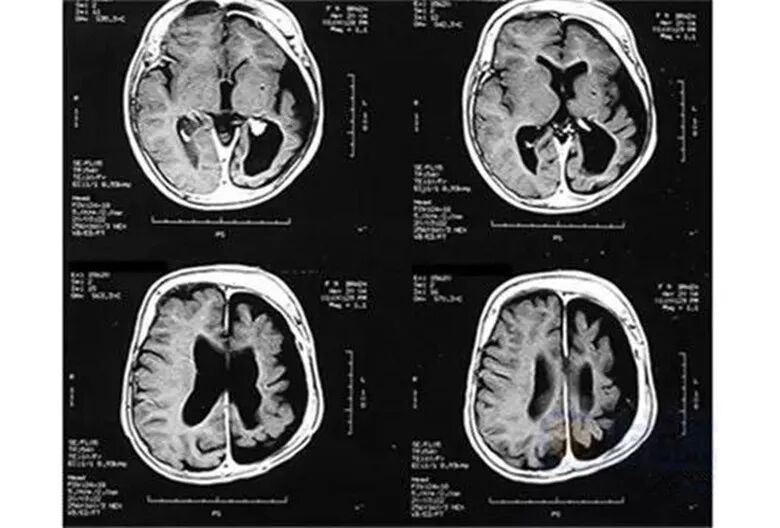

鲜红斑痣长在面部时,若伴发青光眼时则叫脑-三叉神经血管瘤病综合征 Sturge–Weber syndrome(斯-韦二氏综合征),常合并癫痫(75~90%)、智力发育迟缓、大脑同侧多发性血管瘤。

CT 可显示钙化,脑萎缩,同侧脉络丛扩大和引流静脉畸形。MRI 造影可显示软脑膜血管瘤,甚至新生儿也可显示。